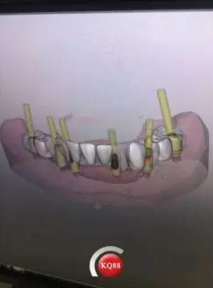

1)術(shù)前檢查,拍攝臨床照片及CBCT檢查,制取活動(dòng)義齒參考模型,指導(dǎo)后期最終修復(fù)的牙齒排列

2)術(shù)前準(zhǔn)備及手術(shù)過(guò)程,測(cè)量血壓及血糖,簽種植知情同意書(shū);嚴(yán)格遵循無(wú)菌操作,局麻下采用微創(chuàng)技術(shù)于323436分別植入osstem4.0X10,4.0X10,4.5X7; 434446分別植入osstem4.0X1O,4.0X10,4.5X7.初期穩(wěn)定性均達(dá)到了35N.CM以上;嚴(yán)密縫合,止血,種植體位點(diǎn)和方向與設(shè)計(jì)一致。